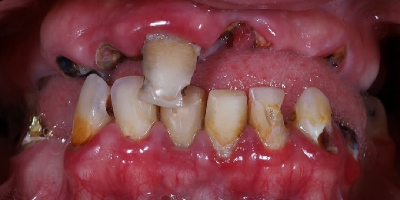

Case Study: Full Mouth Restoration

- Procedure: Implants, Crowns, and Bridges

- Patient: Michael B. (from Texas, USA)

- Problem: Failing teeth, multiple missing teeth.

- Time: 3 Days (Trip 1) Time: 7 Days (Trip 2)